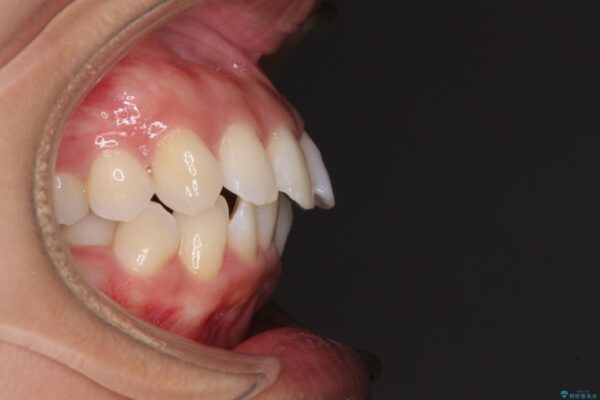

治療前

• 抜歯矯正で唇を閉じやすく 目立たないワイヤー装置 治療前画像